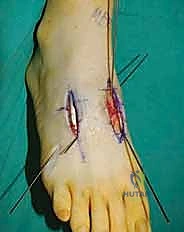

2. الشق الجراحي والوصول للمفاصل

يتم عمل شق جراحي واحد أو شقين (أحدهما في الجزء العلوي الداخلي والآخر في الجزء الخارجي) للوصول إلى مفاصل منتصف القدم دون الإضرار بالأوتار الحيوية والأعصاب والأوعية الدموية. يتم استخدام تقنيات الجراحة الدقيقة (Microsurgery) للحفاظ على الأنسجة المحيطة السليمة.

6. التثبيت الصلب (Rigid Fixation)

لضمان التحام العظام لتصبح عظمة واحدة صلبة، يجب تثبيتها بقوة هائلة حتى لا تتحرك أثناء فترة الشفاء. يتم استخدام مسامير معدنية متطورة (Screws)، أو شرائح معدنية خاصة (Plates)، أو دبابيس طبية متخصصة (Staples) مصنوعة من التيتانيوم الآمن على الجسم.

7. الإغلاق والضماد

بعد التأكد التام من وضع العظام وثباتها باستخدام جهاز الأشعة السينية داخل غرفة العمليات (C-Arm)، يتم إغلاق الشقوق الج